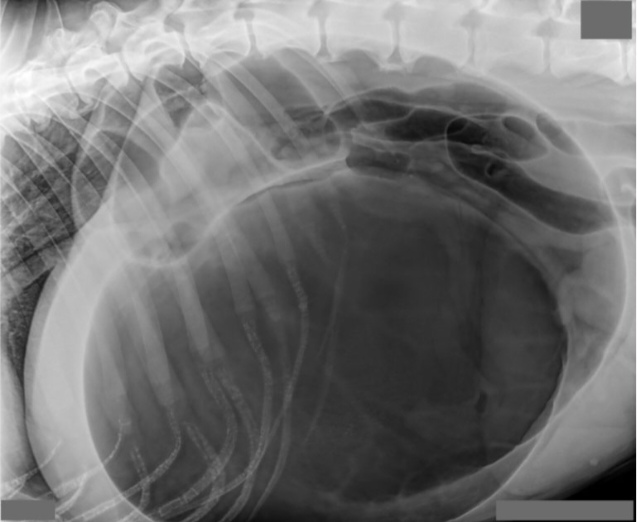

Kuukauden Leikkauspotilas: Koiran mahalaukun vierasesine